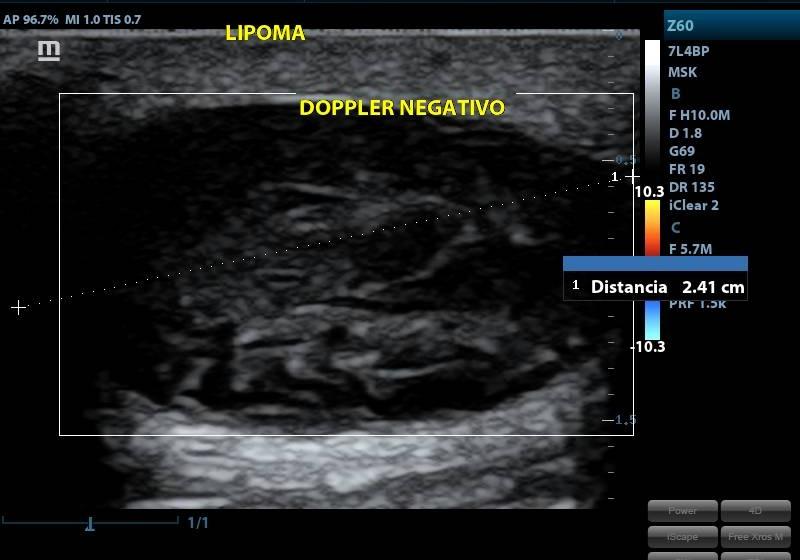

ECOGRAFIA PARTES BLANDAS

SERVICIOECOGRAFIA

PRESENTACIÓNECOGRAFIA

CONDICIÓNNO REQUIERE PREPARACION PREVIA

TIEMPO20 MINUTOS

TIPO RESULTADOSIMAGENES ECOGRAFICAS

ESPECIFICACIONESSE ESTUDIA: MAMAS TIROIDES CUELLO ABDOMEN INGLE